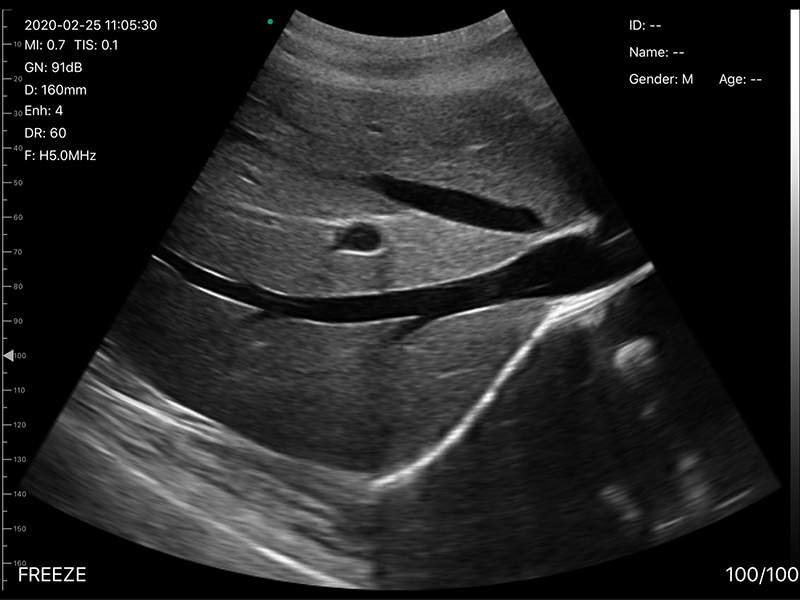

• 扫描深度:90/160/220/305mm,可调

• 穿刺辅助功能:平面内穿刺引导线功能,平面外

穿刺引导与血管自动测量功能,针尖显影增强功能